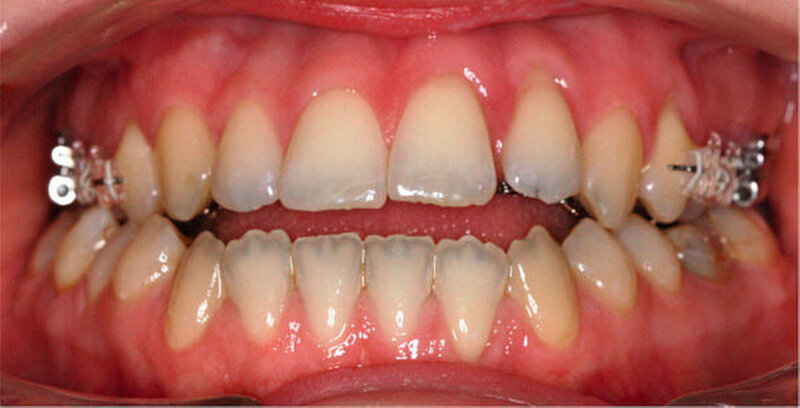

Zwölf Monate nach Beginn der orthodontischen Therapie wurde die bimaxilläre Umstellungsosteotomie durchgeführt. Für die postoperative intermaxilläre Fixierung wurden vestibulär im Seitenzahnbereich Keramikbrackets geklebt (Abbildung 4).